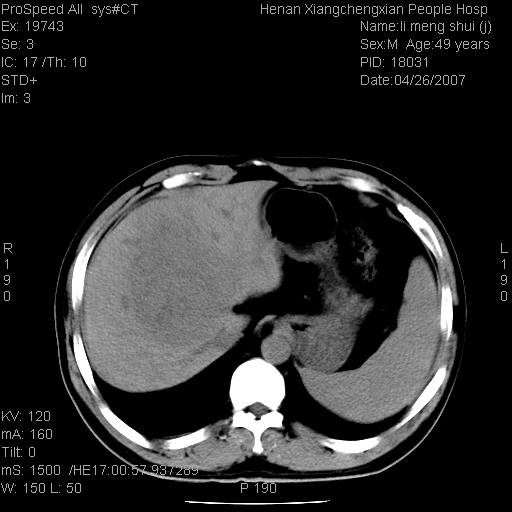

| 患者,男,49岁, 腹疼伴恶心\\呕吐20天,20天前无明显诱因出现右上腹部疼痛,钝疼,无放射,伴恶心\\呕吐,不伴发热.患者不愿增强. b超:肝脏右叶实性占位. ct:肝脏右叶可见一巨块状圆形低密度影,大小约93mm*84mm,其内可见点状高密度影,胆囊、胰腺、脾脏大小、形态及密度未见异常,腹膜后间隙未见肿大淋巴结影。 印象:肝脏右叶巨大肿块,性质待定,建议增强并穿刺活检进一步确诊。 ct平扫: ![]() ![]() ![]() ![]() ![]() ![]() ![]() ![]() ![]() ![]() ![]() ![]() ![]() ![]() ![]() ![]() ![]() 肝脏右叶肿块ct引导下穿刺活检术 患者于16时05分仰卧于ct检查台上,首先行肝脏ct扫描确定进针位置、深度、角度。在局麻下行ct引导下肝脏右叶肿块穿刺活检术。常规消毒、铺巾、局麻。在ct引导下使活检针经右侧腋中线、第9肋间隙垂直胸壁进针90mm,针头进入病变预定位置。在病变预定位置多点、多方向抽取小米样病变组织多块,涂片五张送病理检查。术后穿刺点局部无出血,未出现腹腔积液等并发症。术中及术后患者生命体征稳定,手术于17时10分成功完成。患者安返病房。 穿刺片 ![]() ![]() ![]() ![]() ![]() ![]() ![]() ![]() ![]() ![]() ![]() ![]() ![]() ![]() ![]() ![]() 病理结果肝细胞癌 ![]() 原贴地址:http://www.radinet.com.cn/forum_view.asp?forum_id=4&view_id=24130 ok |